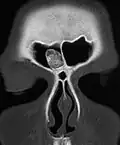

Остеома лобной пазухи на рентгене

Остеома лобной пазухи на компьютерном томографе